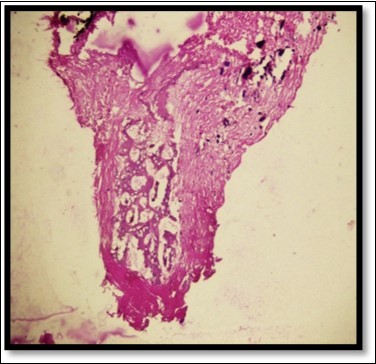

During the next visit local anesthesia was given. The lesion was excised with the help of soft tissue laser and sent for histological examination. (Figure 2) Histological report confirmed the lesion is Peripheral cemento-ossifying Fibroma. Histological analysis showed lesional tissue comprising of both trabecular bone and woven bone. Periphery of the lesion showed numerous globular and irregular cementum like calcification. In most areas these calcification coalesced with each other forming bigger calcification. The supporting connective tissue stroma was loose fibrillar with less cellularity. Detached overlying parakeratinized epithelium was observed in one area. (Figure 3) Post operative evaluation revealed normal healing after one month. (Figure 4)

Figure 3.Histologically H & E stained section shows trabecular bone and woven bone more towards the center of the lesion